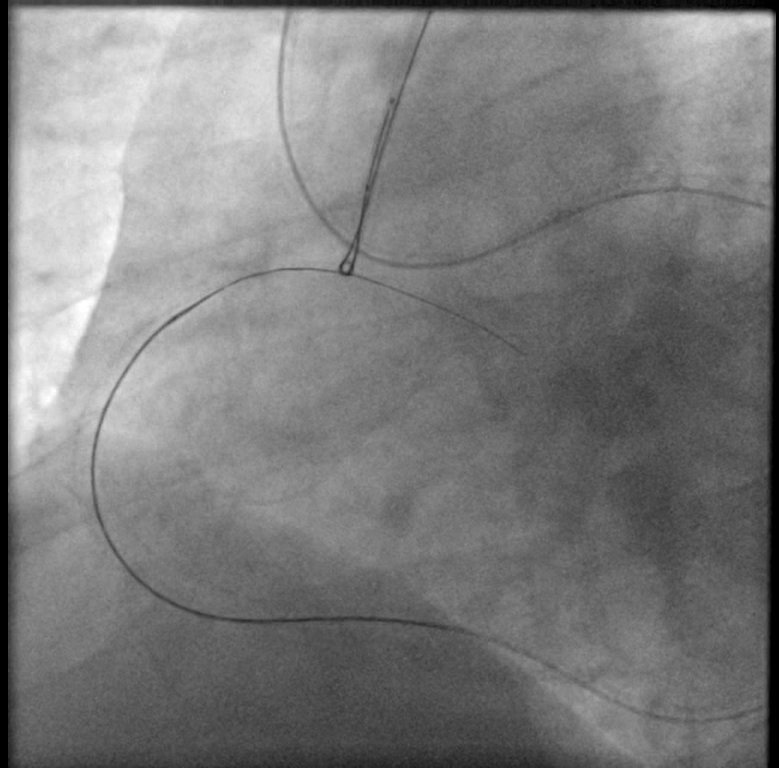

Dual femoral access , Dual injection through AL1 7F & XB4 7F Target vessel assessment ( RCA ) with calculation of J-CTO score then deciding which strategy we decided a Trial antegrade, If failed , Retrograde through septals , If failed , shift to epicardial collateral.Antegrade Trial with GAIA Wires , Corsair MC failed , Retrograde trial through septals failed as it seems not connected shifting strategy to epicardial : Sion blue navigated through epicardial collaterals , corsair 150 MC successfully passed through PL branch MC advanced to distal Cap & GAIA 2nd wire successfully pierced distal cap , but failed to entre antegrade guide Trial snaring through AL guiding by a home made snare but failed , Guiding changed to JR with successful snaring of wire into antegrade guide followed by MCPilot 50 wire introduced through retrograde MC ( Rendezvous Technique , Reverse TIP IN ) then MC Withdrawn we started conventional PCI with Antegrade Balloon dilatation 2.5 * 15 mm semicompliant then 3.5 * 15 mm NC balloons Then stenting with 2 overlapping DES with postdialtation with 4*15 NC balloon with final good angiographic results